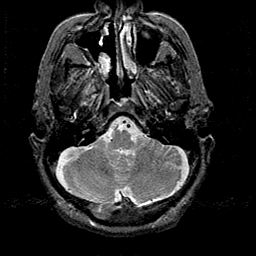

Alzheimer's disease MR T2-weighted -- Slice #9

[Home][Help][Clinical][Tour 1][Tour 2] Slice 9